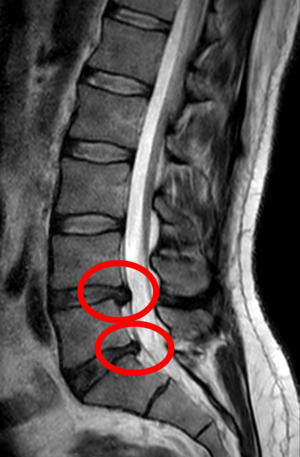

التصوير بالرنين المغناطيسي للانزلاق الكبير (على اليمين) بين الفقرتين القطنيتين الرابعة والخامسة.

انزلاق شديد إلى حد ما بين الفقرتين القطنيتين الرابعة والخامسة.

مثال على انزلاق غضروفي في الفقرات القطنية الخامسة والعجزية الأولى في العمود الفقري القطني.